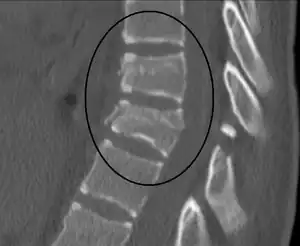

Chance fracture

A Chance fracture is a type of vertebral fracture that results from excessive flexion of the spine.[8][9] Symptoms may include abdominal bruising (seat belt sign), or less commonly paralysis of the legs.[4][10] In around half of cases there is an associated abdominal injury such as a splenic rupture, small bowel injury, pancreatic injury, or mesenteric tear.[3][5] Injury to the bowel may not be apparent on the first day.[11]

| A Chance fracture of T10 and fracture of T9 due to a seatbelt during an MVC. | |

The cause is classically a head-on motor vehicle collision in which the affected person is wearing only a lap belt.[2] Being hit in the abdomen with an object like a tree or a fall may also result in this fracture pattern.[12][10] It often involves disruption of all three columns of the vertebral body (anterior, middle, and posterior).[7][6] The most common area affected is the lower thoracic and upper lumbar spine.[6] A CT scan is recommended as part of the diagnostic work-up to detect any potential abdominal injuries.[5] The fracture is often unstable.[1]

A CT scan of the chest, abdomen, and pelvis is recommended as part of the diagnostic work-up to detect any potential abdominal injuries.[5][10] MRI may also be useful.[10] The fracture is often unstable.[1]